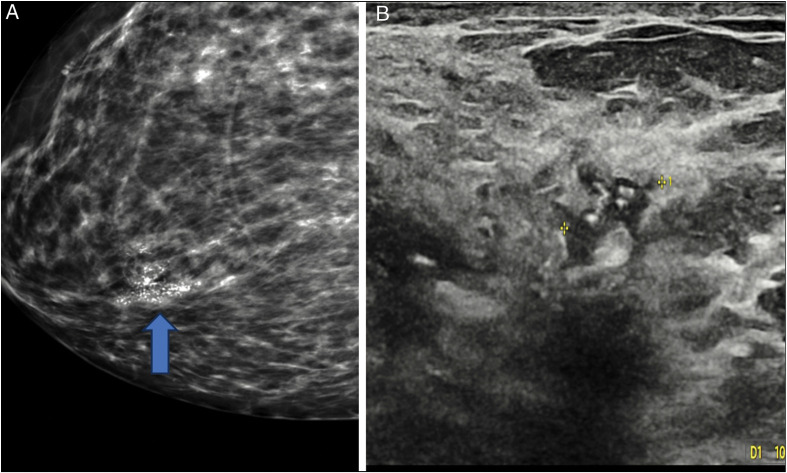

Background: Approximately 80% of ductal carcinoma in situ (DCIS) cases are asymptomatic and manifest as microcalcifications, usually detected on screening mammograms. Stereotactic biopsy is used as the primary modality for histopathologic diagnosis. Ultrasonography has been relied upon as a potentially viable alternative for early breast cancer detection, especially in low- and medium-income countries.

Results: Eighty women included were within the age range of 46-79 years, with mean age of 60 years. Background breast density was predominantly fatty in 51/80 (63.8%), without any correlation with mammographic abnormalities. Microcalcifications were classified as indeterminate (M3) in 42/80 (52.5%), while suspicious (M4) and malignant (M5) types were seen in 38/80 (47.5%). No targeted sonographic abnormalities were noted in 69 (86.2%) of the patients, while 11 (13.8%) had sonographic abnormalities. The predominant sonographic feature was non-mass hypoechogenicity in 6/11(55%). There was a correlation between mammographic code, lesion size, and ultrasonic abnormality, with 9/11 (81.8%) patients with sonographic lesions having suspicious and malignant type calcifications. The mean mammographic lesion size was significantly greater in women with abnormal ultrasound findings, 42 vs. 20 mm. Histological tumour grade was high grade in 10/11 (90.9%) lesions.

Conclusion: The accuracy of breast ultrasonography as an adjunct in the detection of screen-detected microcalcifications and subsequent guided biopsy is higher when dealing with malignant type microcalcifications >15 mm in size.